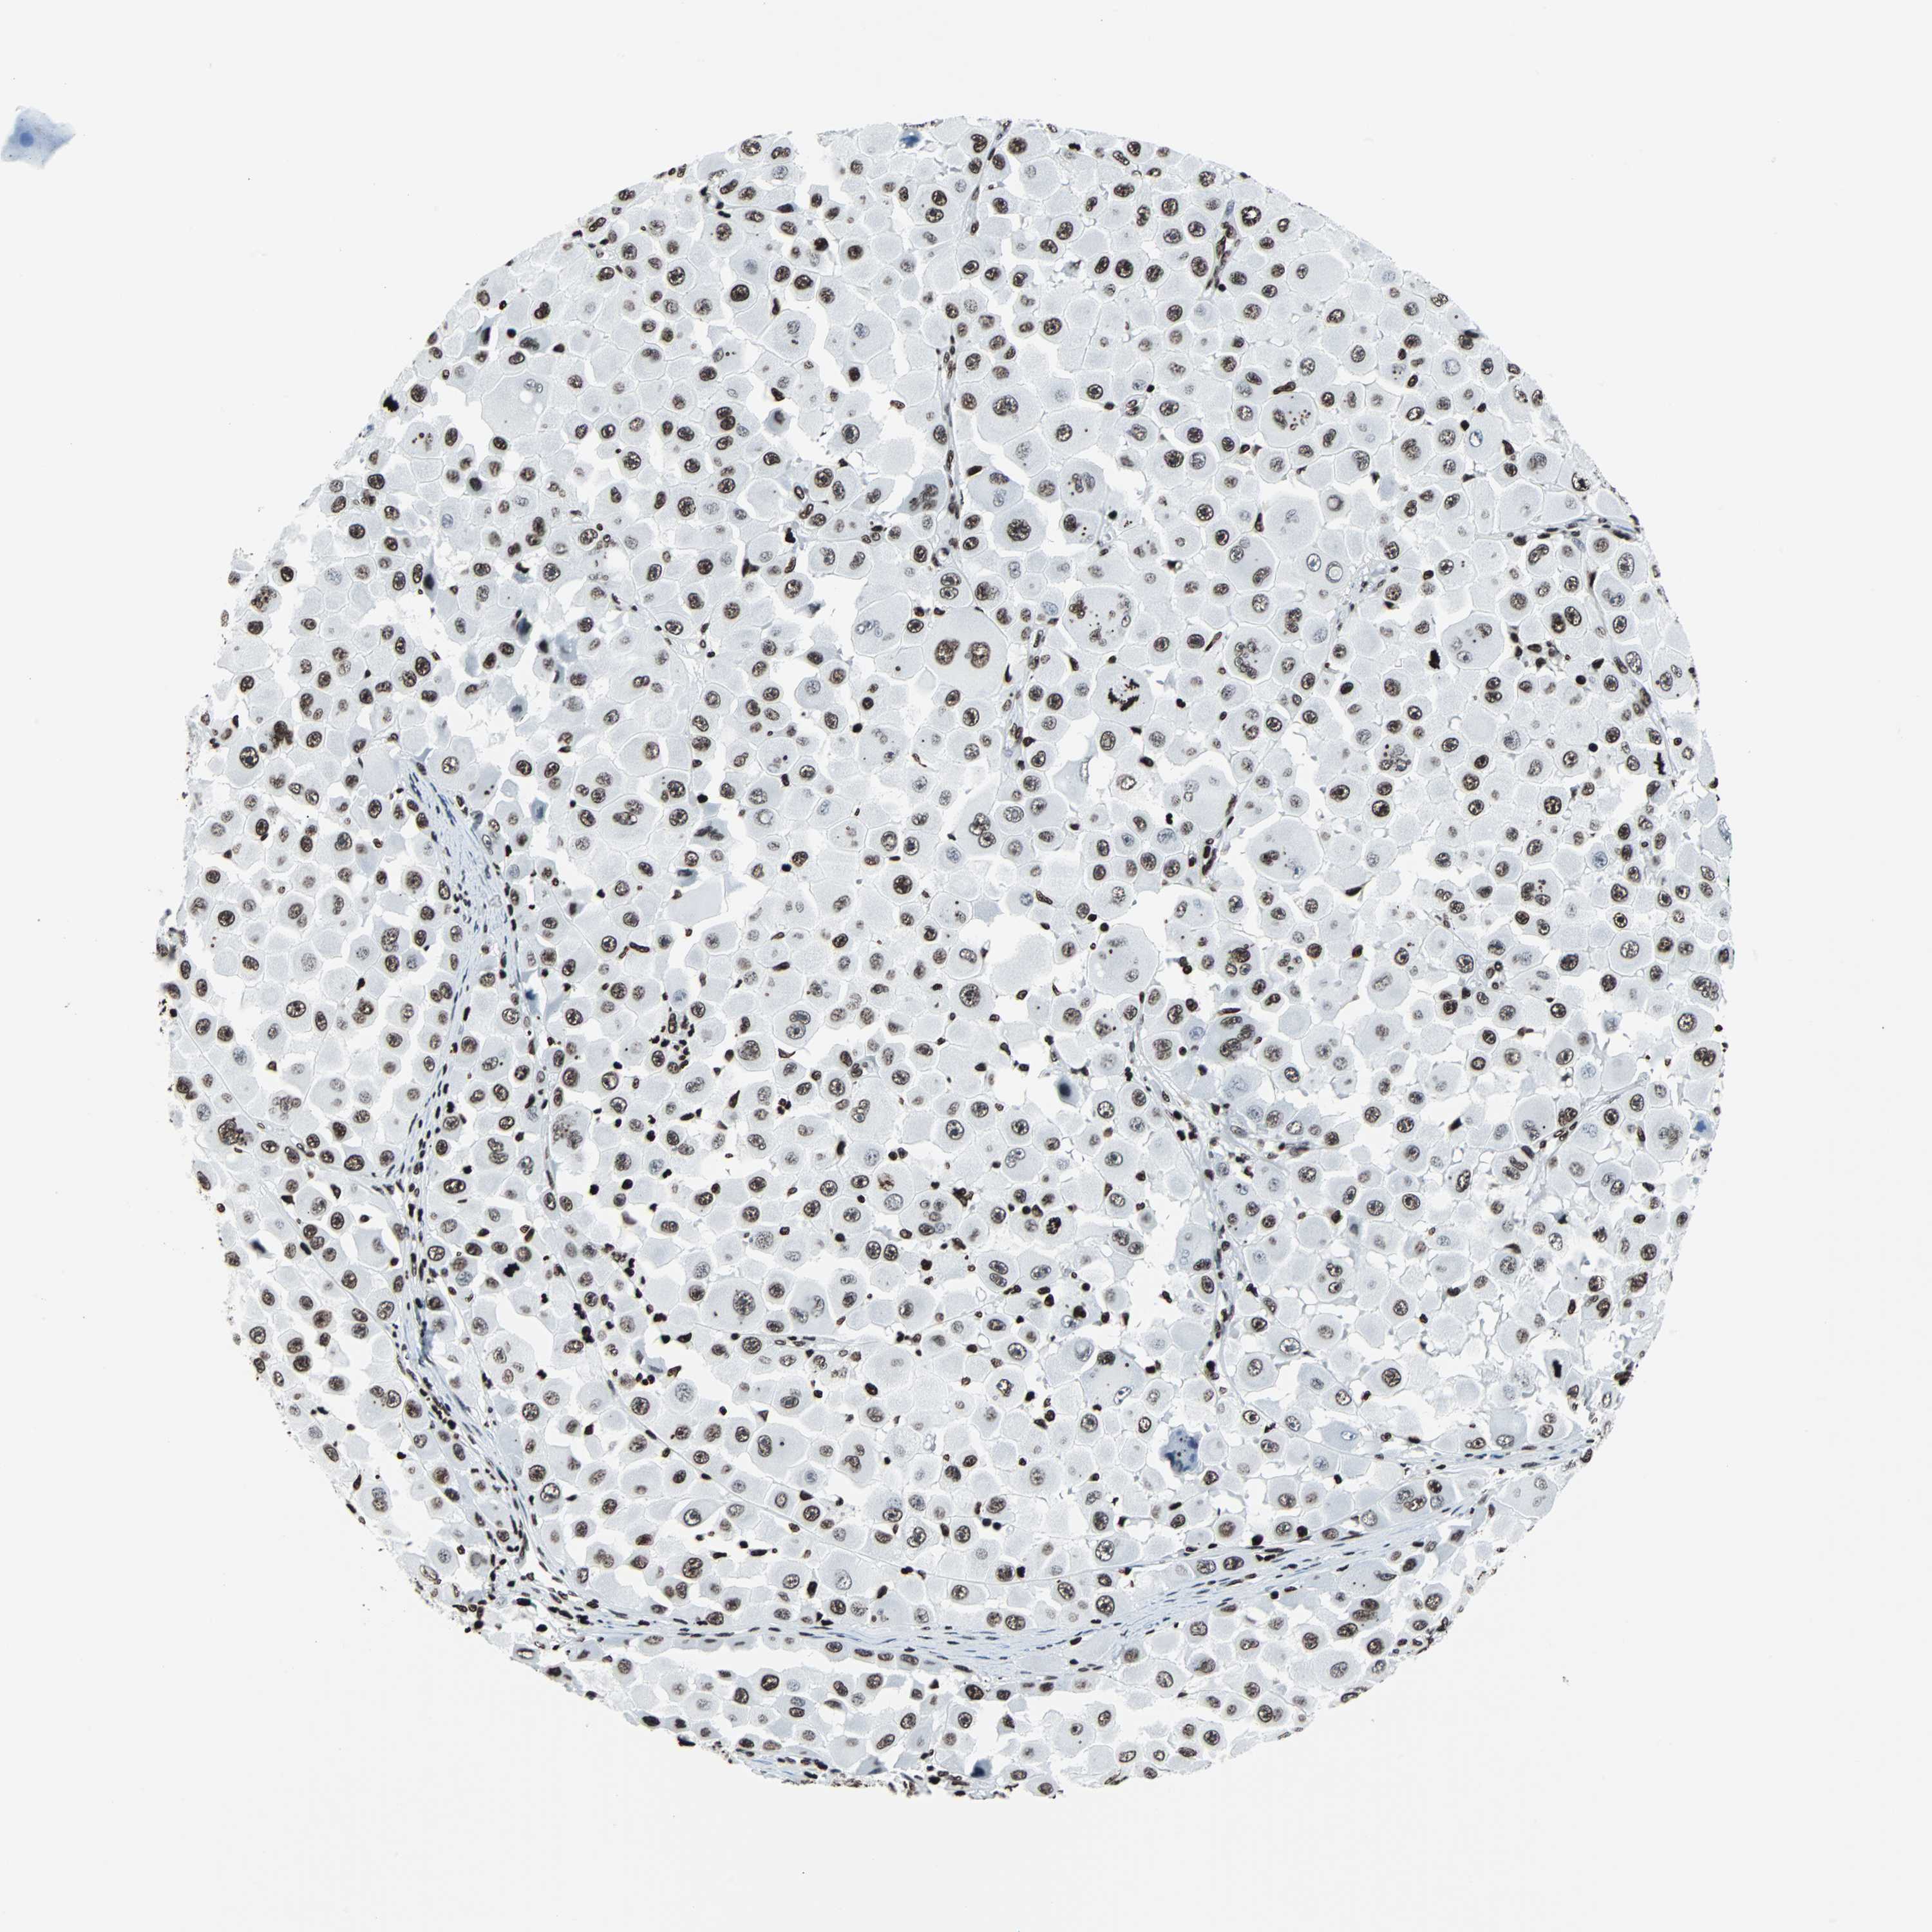

MELANOMA - Protein expressioni

A mouse-over function shows sample information and annotation data. Click on an image to view it in a full screen mode. Samples can be filtered based on level of antibody staining by selecting one or several of the following categories: high, medium, low and not detected. The assay and annotation is described here.

Note that samples used for immunohistochemistry by the Human Protein Atlas do not correspond to samples in the TCGA dataset.

Antibody stainingi

Antibody staining in the annotated cell types in the current human tissue is reported as not detected, low, medium, or high, based on conventional immunohistochemistry profiling in selected tissues. This score is based on the combination of the staining intensity and fraction of stained cells.

Each image is clickable and will lead to virtual microscopy that enables deeper exploration of all samples and also displays staining intensity scores, fraction scores and subcellular localization as well as patient and tissue information for each sample.

Antibody CAB007814

Staining

High

Medium

Low

Not detected

Intensity

Strong

Moderate

Weak

Negative

Quantity

>75%

75%-25%

<25%

None

Location

Nuclear

Cytoplasmic/membranous

Cytoplasmic/membranous,nuclear

Malignant melanoma, NOS